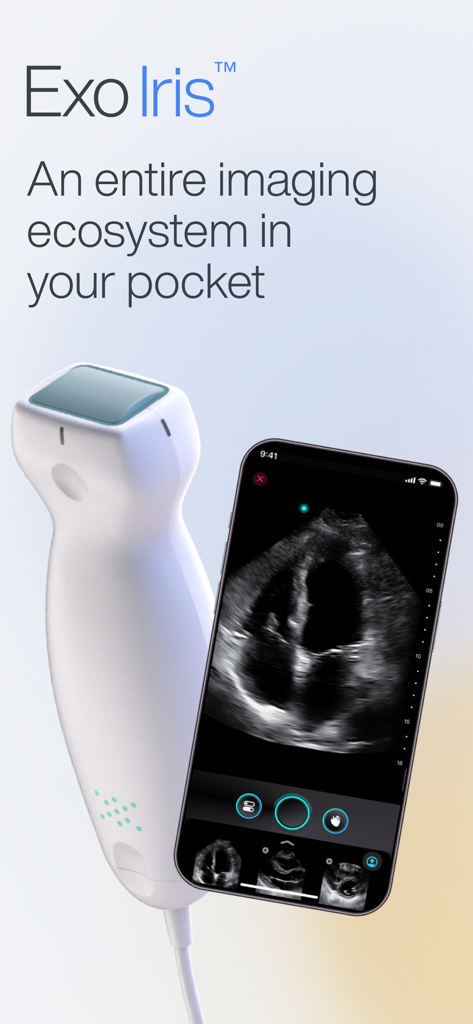

Exo Iris™ redefines the medical imaging ecosystem, blending high-performance proprietary silicon technology with real-time AI to deliver clinical answers when seconds count.

Versatile 3-in-1 Imaging

Perform cardiac, lung, and vascular scans with a single handheld device, eliminating the need for multiple probes and bulky hardware.